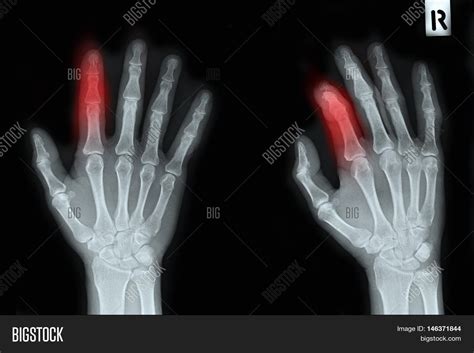

Diagnosing a Broken Index Finger

Diagnosing a broken index finger typically involves a physical examination and imaging tests. Your healthcare provider will:

• Examine the injured finger to assess the extent of the damage.

• Order X-rays to visualize the bone and determine the type and severity of the fracture.

• In some cases, additional imaging tests such as CT scans or MRIs may be required for a more detailed view.